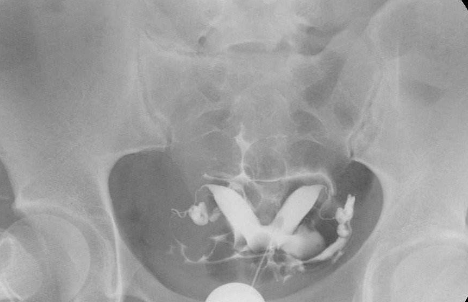

相關檢查:

子宮輸卵管造影

雙角子宮圖片